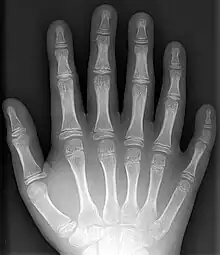

An x-ray of a hand with a supernumerary digit (polydactyly)

Supernumerary body parts are most commonly a congenital disorder involving the growth of an additional part of the body and a deviation from the body plan. Body parts may be easily visible or hidden away, such as internal organs.